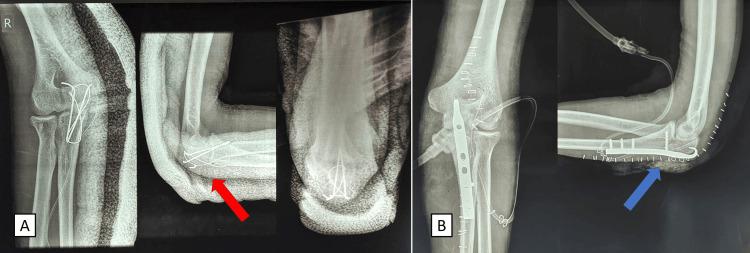

Olecranon fractures are common in orthopedic wards and can be traumatic or pathological in origin. There are very few cases of bilateral olecranon fractures without any associated injuries to the long bones in the literature. We present a unique case of a young 21-year-old male who has an isolated bilateral olecranon fracture following a road traffic accident. The patient had a closed fracture of the ulna on both sides without any associated injuries or neurovascular compromise. Since the patient was young and had good muscle strength preoperatively, we planned fixation of both sides. The patient underwent open reduction and internal fixation with tension band wiring on the right side, which was his dominant side. The left side was operated on by open reduction and internal fixation with an anatomical plate. The patient was started on elbow range of motion on the right side from the secondpostoperative day and started basic activities such as having food independently by the 10th day postoperatively. The physiotherapy was continued in a stepwise manner, and by the sixth week, the patient had a full range of motion on both sides. The patient had resumed his activities of daily living independently by the sixthweek following the surgery. Such cases are rare, and a case-based management plan must be devised for each patient, considering contributing factors such as age, bone quality, osteoporosis, underlying medical comorbidities, functional demands, and muscle strength. We demonstrated a good clinical and radiological outcome by using tension band wiring on the dominant side with a stable olecranon fracture and plating done on the non-dominant side, which had an unstable displaced olecranon fracture.

鹰嘴骨折在骨科病房较为常见,其成因可能是创伤性的或病理性的。文献中极少有双侧鹰嘴骨折且长骨无任何相关损伤的病例。我们报告一例独特病例,一名21岁年轻男性在道路交通事故后发生孤立性双侧鹰嘴骨折。患者双侧尺骨闭合性骨折,无任何相关损伤或神经血管损伤。由于患者年轻且术前肌力良好,我们计划对双侧进行固定。患者右侧(优势侧)接受切开复位张力带钢丝内固定术,左侧采用解剖钢板切开复位内固定术。术后第二天开始右侧肘关节活动度训练,术后第10天开始独立进食等基本活动。物理治疗逐步进行,到第六周时,患者双侧肘关节活动度恢复正常。术后第六周,患者已能独立恢复日常生活活动。此类病例罕见,必须针对每位患者制定基于病例的管理计划,考虑年龄、骨质、骨质疏松、基础疾病、功能需求和肌力等相关因素。我们通过对优势侧稳定的鹰嘴骨折采用张力带钢丝固定,对非优势侧不稳定移位的鹰嘴骨折采用钢板固定,取得了良好的临床和影像学效果。